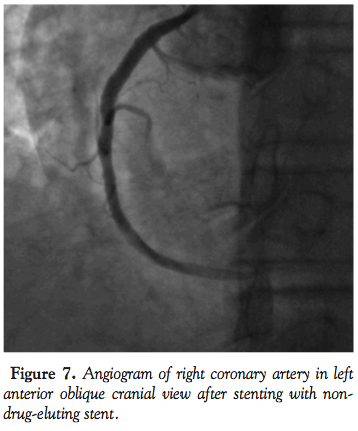

negative suction, the guide catheter was slowly withdrawn from the artery and out of the femoral sheath. Flushing of the guide catheter revealed chunks of intact thrombus that matched the filling defect (Figure 4). While all this was done, the stabilizer wire was in the RCA to ensure access to the distal RCA. There was significant improvement in blood pressure of the patient along with relief in the chest pain. A 7 Fr guide catheter was passed over the stabilizer wire and the RCA was engaged (Figure 5). Angiogram revealed a widely patent artery with TIMI III flow and a residual stenosis of 80% in mid segment of the RCA (Figure 6). The lesion was stented with a non-drug-eluting Prokinetic stent 4 mm x18 mm (Biotronik AG). Post-dilatation, patient developed slow flow, which was successfully managed. Final angiogram showed a well-expanded stent with TIMI III flow (Figure 7). Post-procedure hospital course of the patient was uncomplicated and he was discharged on dual antiplatelet regimen on day 4.